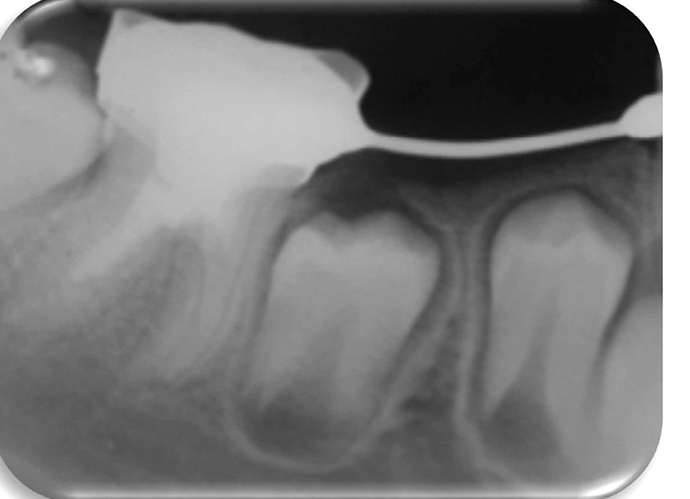

Streszczenie: Wprowadzenie. Przedstawiono i omówiono wyniki leczenia pięciu przypadków klinicznych metodą rewaskularyzacji miazgi, z monitorowaniem klinicznym i radiologicznym. Niedojrzałe zęby stałe z martwicą miazgi i ze zmianami okołowierzchołkowymi stanowią wyzwanie dla stomatologów, ponieważ po zastosowaniu apeksyfikacji ząb staje się podatny na złamania, jako że jego korzeń nie ulega dalszemu wzrostowi, a ściany kanału korzeniowego są cienkie. Rewaskularyzacja stała się alternatywą do zlikwidowania tych niedogodności, umożliwiając zamknięcie wierzchołka, dalszy rozwój korzenia i pogrubienie zębiny ścian kanału korzeniowego. Opisy przypadków. Pięć zdiagnozowanych klinicznie i radiologicznie niedojrzałych zębów stałych z martwicą miazgi leczono metodą rewaskularyzacji. Protokół terapeutyczny obejmował: dostęp do komory miazgi, obfite przepłukanie NaOCl, założenie pasty trójantybiotykowej jako opatrunku wewnątrzkanałowego i tymczasowe zamknięcie ubytku. Wniosek. Omówienie wyników leczenia stanowi materiał do dyskusji na temat różnych materiałów do odbudowy zęba i innych opublikowanych protokołów leczenia.